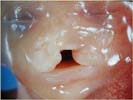

Diagnostic :

Solution de continuité de la lèvre supérieure (coupes frontale et transversale). Elle peut également interrompre le palais. Cette fente palatine associée est plus difficile à rechercher.

En utilisant le plan de coupe passant par le menton et la pointe du nez, et en imprimant des petits mouvements au transducteur, la mise en évidence de l’anomalie ne pose pas de problème.

En coupe transversale : Interruption du maxillaire supérieur.